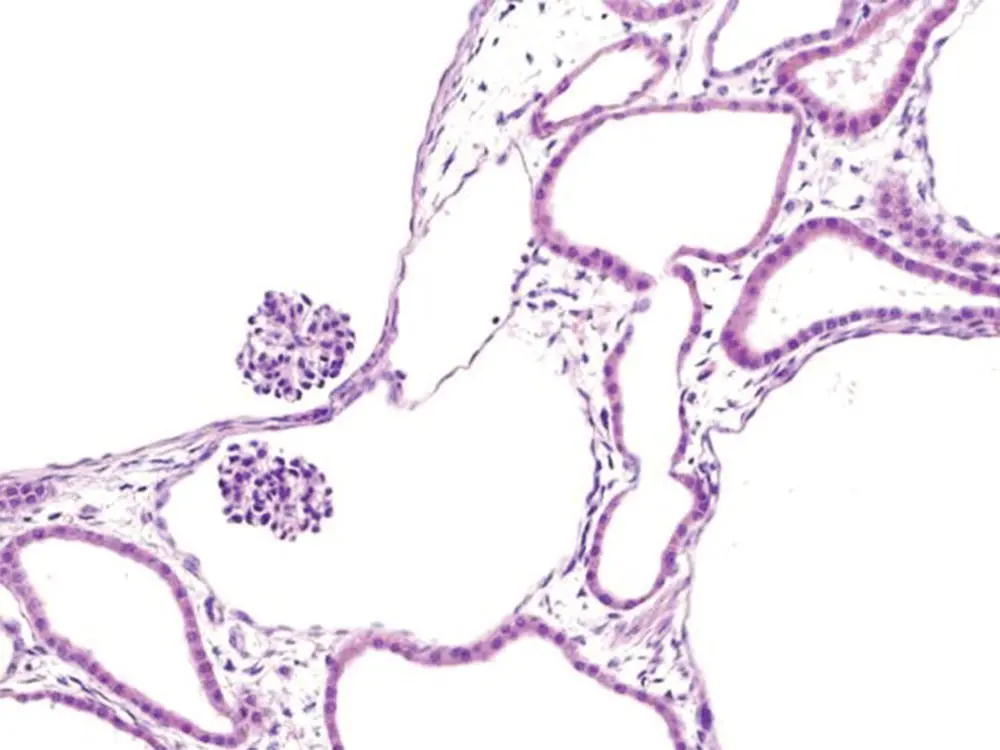

PKDs were the first to be linked definitively to defects in primary immotile cilia. Recognition that polycystin 1 (PKD1), polycystin 2 (PKD2), and nephrocystin 1 (NPHP1) proteins were all localized to the primary cilium/basal body/centrosome provided the first evidence that dysfunctional primary cilia could be involved in the pathogenesis of PKD and nephronophthisis (NPHP) [47, 48]. Since then mutations in dozens of other cilia‐related genes have been directly linked to the development of cystic kidney diseases [49]. The primary cilium on renal tubular epithelial cells projects into the urinary space and appears to act as a mechanosensor in detecting the flow of urine and thereby influencing renal cell division [50]. The primary cilium also regulates the orientation of cell division and disrupted planar cell polarity signaling also contributes to renal cystogenesis [51]. PKD is characterized by grossly enlarged kidneys, due to markedly dilated renal tubules lined by epithelial cells showing increased mitotic activity ( Figure 6.4). In contrast, the polycystic kidneys in NPHP are essentially normal or reduced in size, with low mitotic rates and increased apoptosis of renal tubular epithelium [52] ( Figure 6.5).

Figure 6.4 Polycystic kidney disease. Dilatation of renal tubules in an enlarged kidney due to proliferation of renal epithelium is associated with dysfunctional primary cilia.